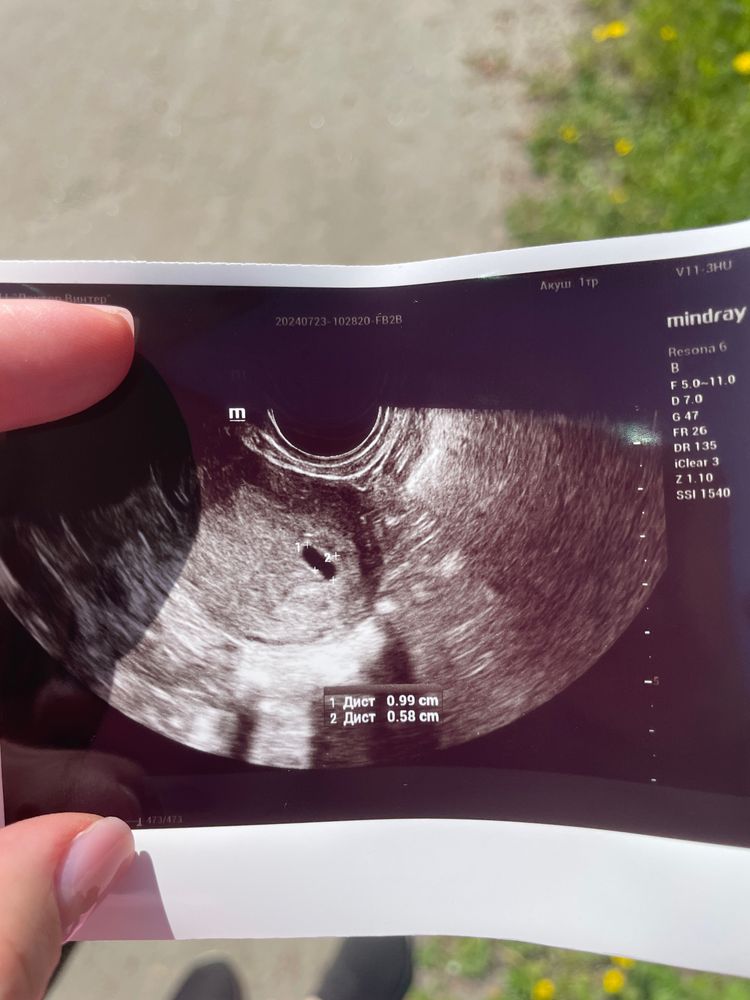

сегодня была на узи - 6 недель и 2 дня , дали понять, что деформация плодного яйца, нет эмбриона и мешочка! Может ли еще появится эмбрион с мешочком или уже нет надежды ? Спасибо заранее за ответ

При таких размерах плодного яйца ещё может ничего не быть, оно маловато для срока, но возможно, была поздняя овуляция. Сходите повторно через неделю-две, через 2 уже будет все ясно.